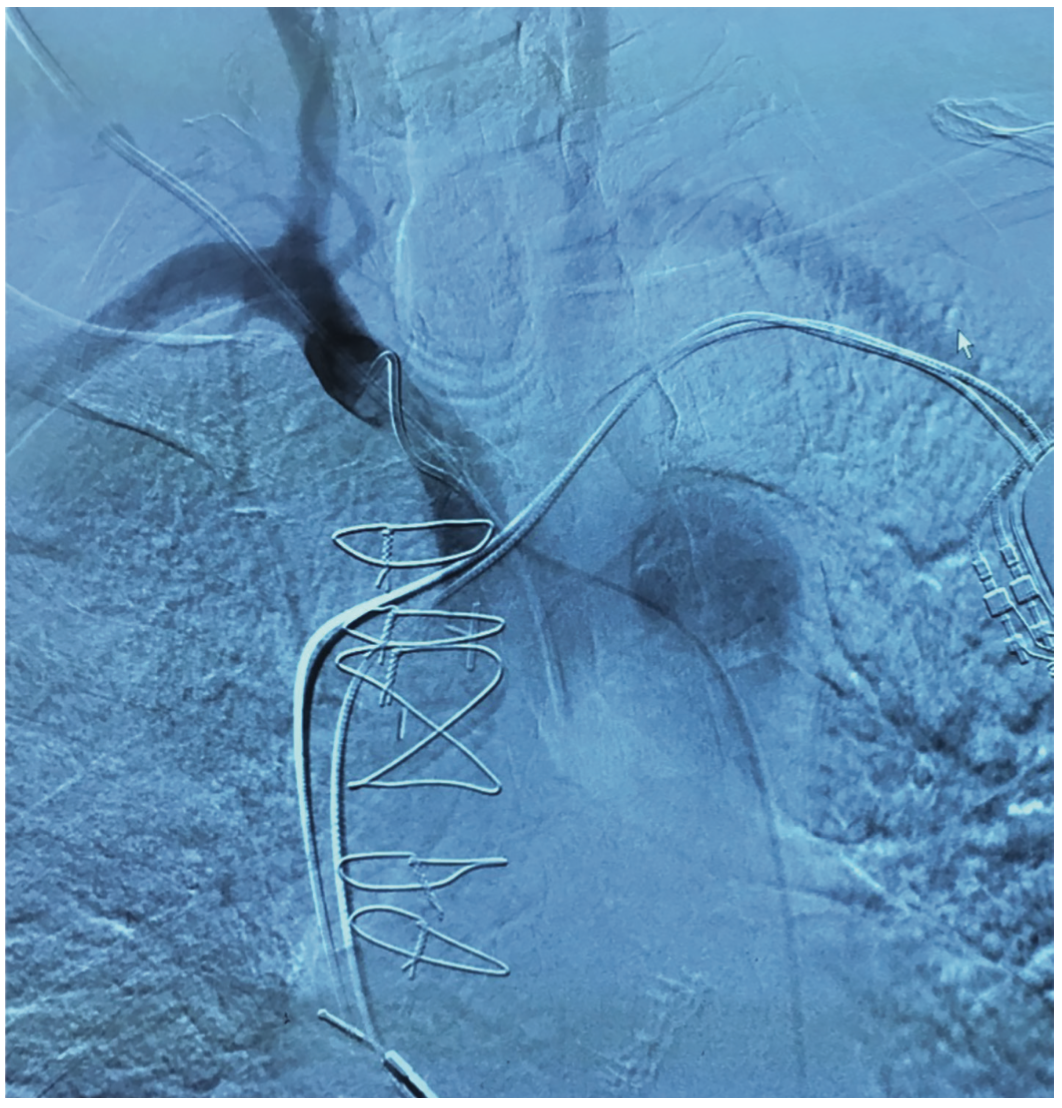

A decision was made to remove the catheter in the cardiac catheterization lab. A 7 French Pinnacle Destination sheath (Terumo) was inserted in to the right femoral artery using the modified Seldinger technique. This alternative artery access was obtained to allow for contrast injections and visualization of the aortic arch and innominate artery. A headhunter catheter was used to engage the right innominate artery and exchanged over a wire for a Tennis Racquet catheter (Boston Scientific). Contrast angiography of the right innominate, subclavian, and carotid artery was obtained using the Tennis Racquet catheter. The triple lumen central venous catheter was then removed over a Newton J wire (Cook), leaving the wire in place. A 6 French Angio-Seal closure device (Terumo) was deployed over the wire. A racquet catheter was used to inject contrast and no leakage was observed. The catheter and sheath were both removed, and the access site in the right groin area was closed via a 6 French Perclose closure device (Abbott Vascular). No immediate complications were noted. Two days later, the patient was discharged, free of complications such as bleeding or stroke.